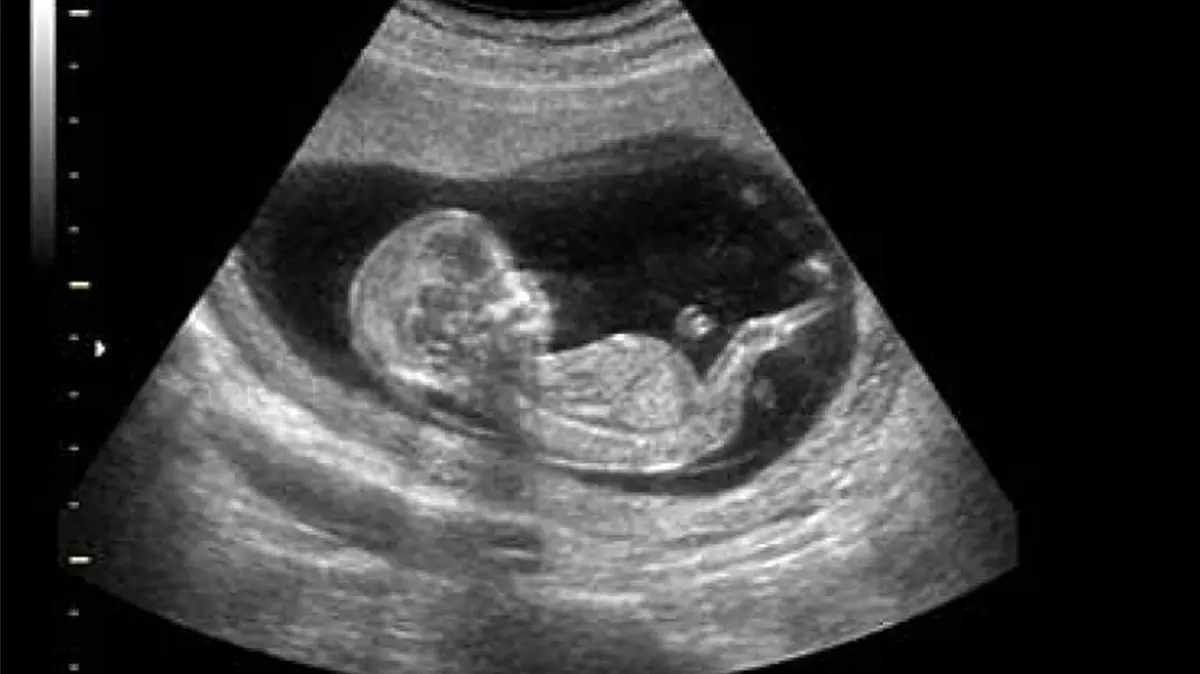

یک پیرزن 81 ساله برزیلی به دلیل درد شکم به پزشک مراجعه می کند و پساز اقدامات اولیه پزشکی و سونوگرافی پزشکان متوجه می شوند که کودکی که این زن 65 سال پیش سقط کرده بود و به دکتر مراجعه نکرده تا به امروز با او همرا بوده است.